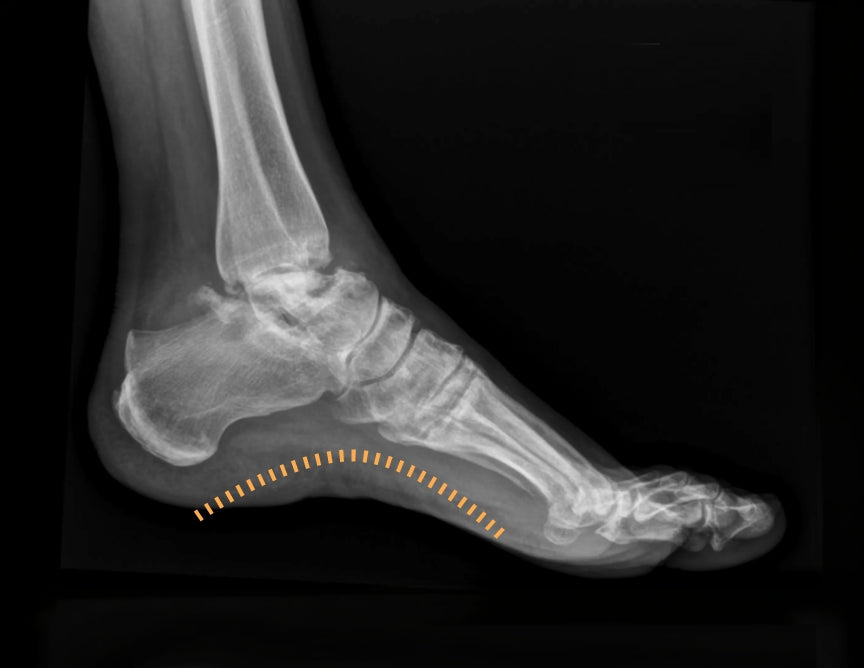

Jeder Schritt ist ein kontinuierlicher Austausch zwischen Körper und Boden und bezieht Tausende sensorischer Rezeptoren mit ein. Bewegung entsteht daraus, wie klar diese Informationen wahrgenommen werden.

Sensorische Unterstützung im Alltag: gezielte Druckveränderungen helfen dem Fuß, klarere Signale zu senden — bei jedem Schritt.

Durch 3D-Druck können Dichte und Form von Zwischensohlen aus Silikonnetz individuell angepasst werden, um die biomechanische Interaktion mit dem Benutzer zu optimieren. Ziel dieser Studie war es, die biomechanischen Auswirkungen solcher Zwischensohlen mit unterschiedlicher Dichte und Fußgewölbeunterstützung zu beurteilen. Es wurden zwei Experimente mit 12 und 9 jungen, körperlich gesunden Teilnehmern durchgeführt, die auf 6 Zwischensohlen mit drei verschiedenen Dichten mit und ohne Fußgewölbeunterstützung gingen. Im ersten Experiment wurden die maximalen Bodenreaktionskräfte, die anfängliche vertikale Belastungsrate, der RMS-Wert der Knöchelinversion/-eversion und die vom Knöchel-Fuß-Komplex absorbierte und erzeugte Kraft beim Gehen auf dem Laufband gemessen. Im zweiten Experiment wurden Spitzendruck, Kontaktfläche und Druckzeitintegral über Rückfuß, Mittelfuß und Vorfuß beim Gehen über dem Boden gemessen. Die Daten wurden auf Gruppen- und Einzelebene analysiert. Im ersten Experiment wurden keine Effekte auf Gruppenebene festgestellt. Im zweiten Experiment reduzierte eine geringere Dichte der Zwischensohle den Spitzendruck auf dem Rück- und Vorderfuß, und die Fußgewölbeunterstützung vergrößerte die Kontaktfläche am Mittelfuß, was die Spitzendrücke am Mittelfuß und das Druckzeitintegral am Mittel- und Vorderfuß reduzierte. Auf individueller Ebene wurden signifikante Auswirkungen des Zwischensohlendesigns festgestellt, die jedoch zwischen den Probanden unterschiedlich waren, was das Fehlen von Auswirkungen auf Gruppenebene erklärt. Zusammenfassend lässt sich sagen, dass die Dichte der Zwischensohle und die Fußgewölbeunterstützung die Biomechanik des Gangs beeinflussten, diese Auswirkungen jedoch eindeutig vom Probanden abhängig waren. Die vorgestellten Ergebnisse unterstützen die Idee, Zwischensohlen an einzelne Benutzer oder Benutzergruppen anzupassen, und demonstrieren den Nutzen von 3D-gedruckten, vernetzten Zwischensohlen zu diesem Zweck.